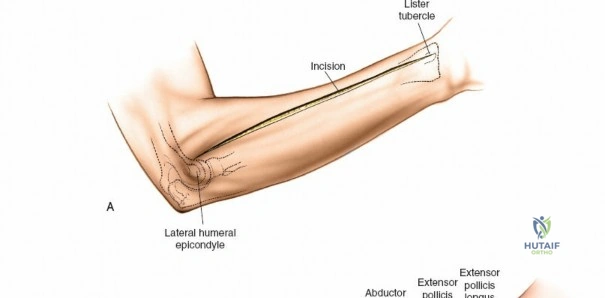

Incision: A curvilinear incision is made from the medial epicondyle, across the antecubital fossa, extending obliquely to the mid-volar aspect of the forearm, and then longitudinally down to the wrist crease, potentially extending into the palm to release the carpal tunnel. The incision should be generous, allowing for wide exposure.

- Key points: The proximal portion of the incision should curve gently to avoid crossing the elbow flexion crease at a right angle, which could lead to contracture. Distally, it should avoid cutting directly over the median nerve at the wrist.

This image shows the standard curvilinear incision for the volar approach, extending proximally from the medial epicondyle, gently crossing the antecubital fossa, and proceeding distally across the mid-forearm to the wrist.

- Key points: The proximal portion of the incision should curve gently to avoid crossing the elbow flexion crease at a right angle, which could lead to contracture. Distally, it should avoid cutting directly over the median nerve at the wrist.

Incision: A separate straight longitudinal incision is made over the dorsal aspect of the forearm, centered approximately between the ulna and radius, extending from just distal to the lateral epicondyle to the wrist.

This image shows the dorsal longitudinal incision, made directly over the extensor compartment, providing access for decompression. -